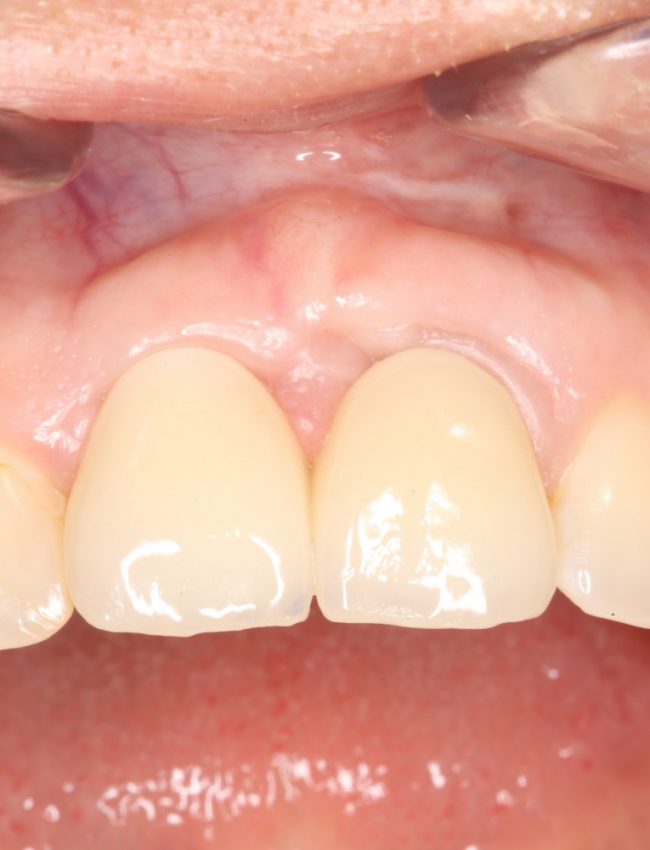

Во-первых, среди докторов нет чёткого представления о том, что считать периимплантитом. Можно ли назвать периимплантитом, например, вот такое?

За фото не переживайте — эту пациентку мы вылечили))))